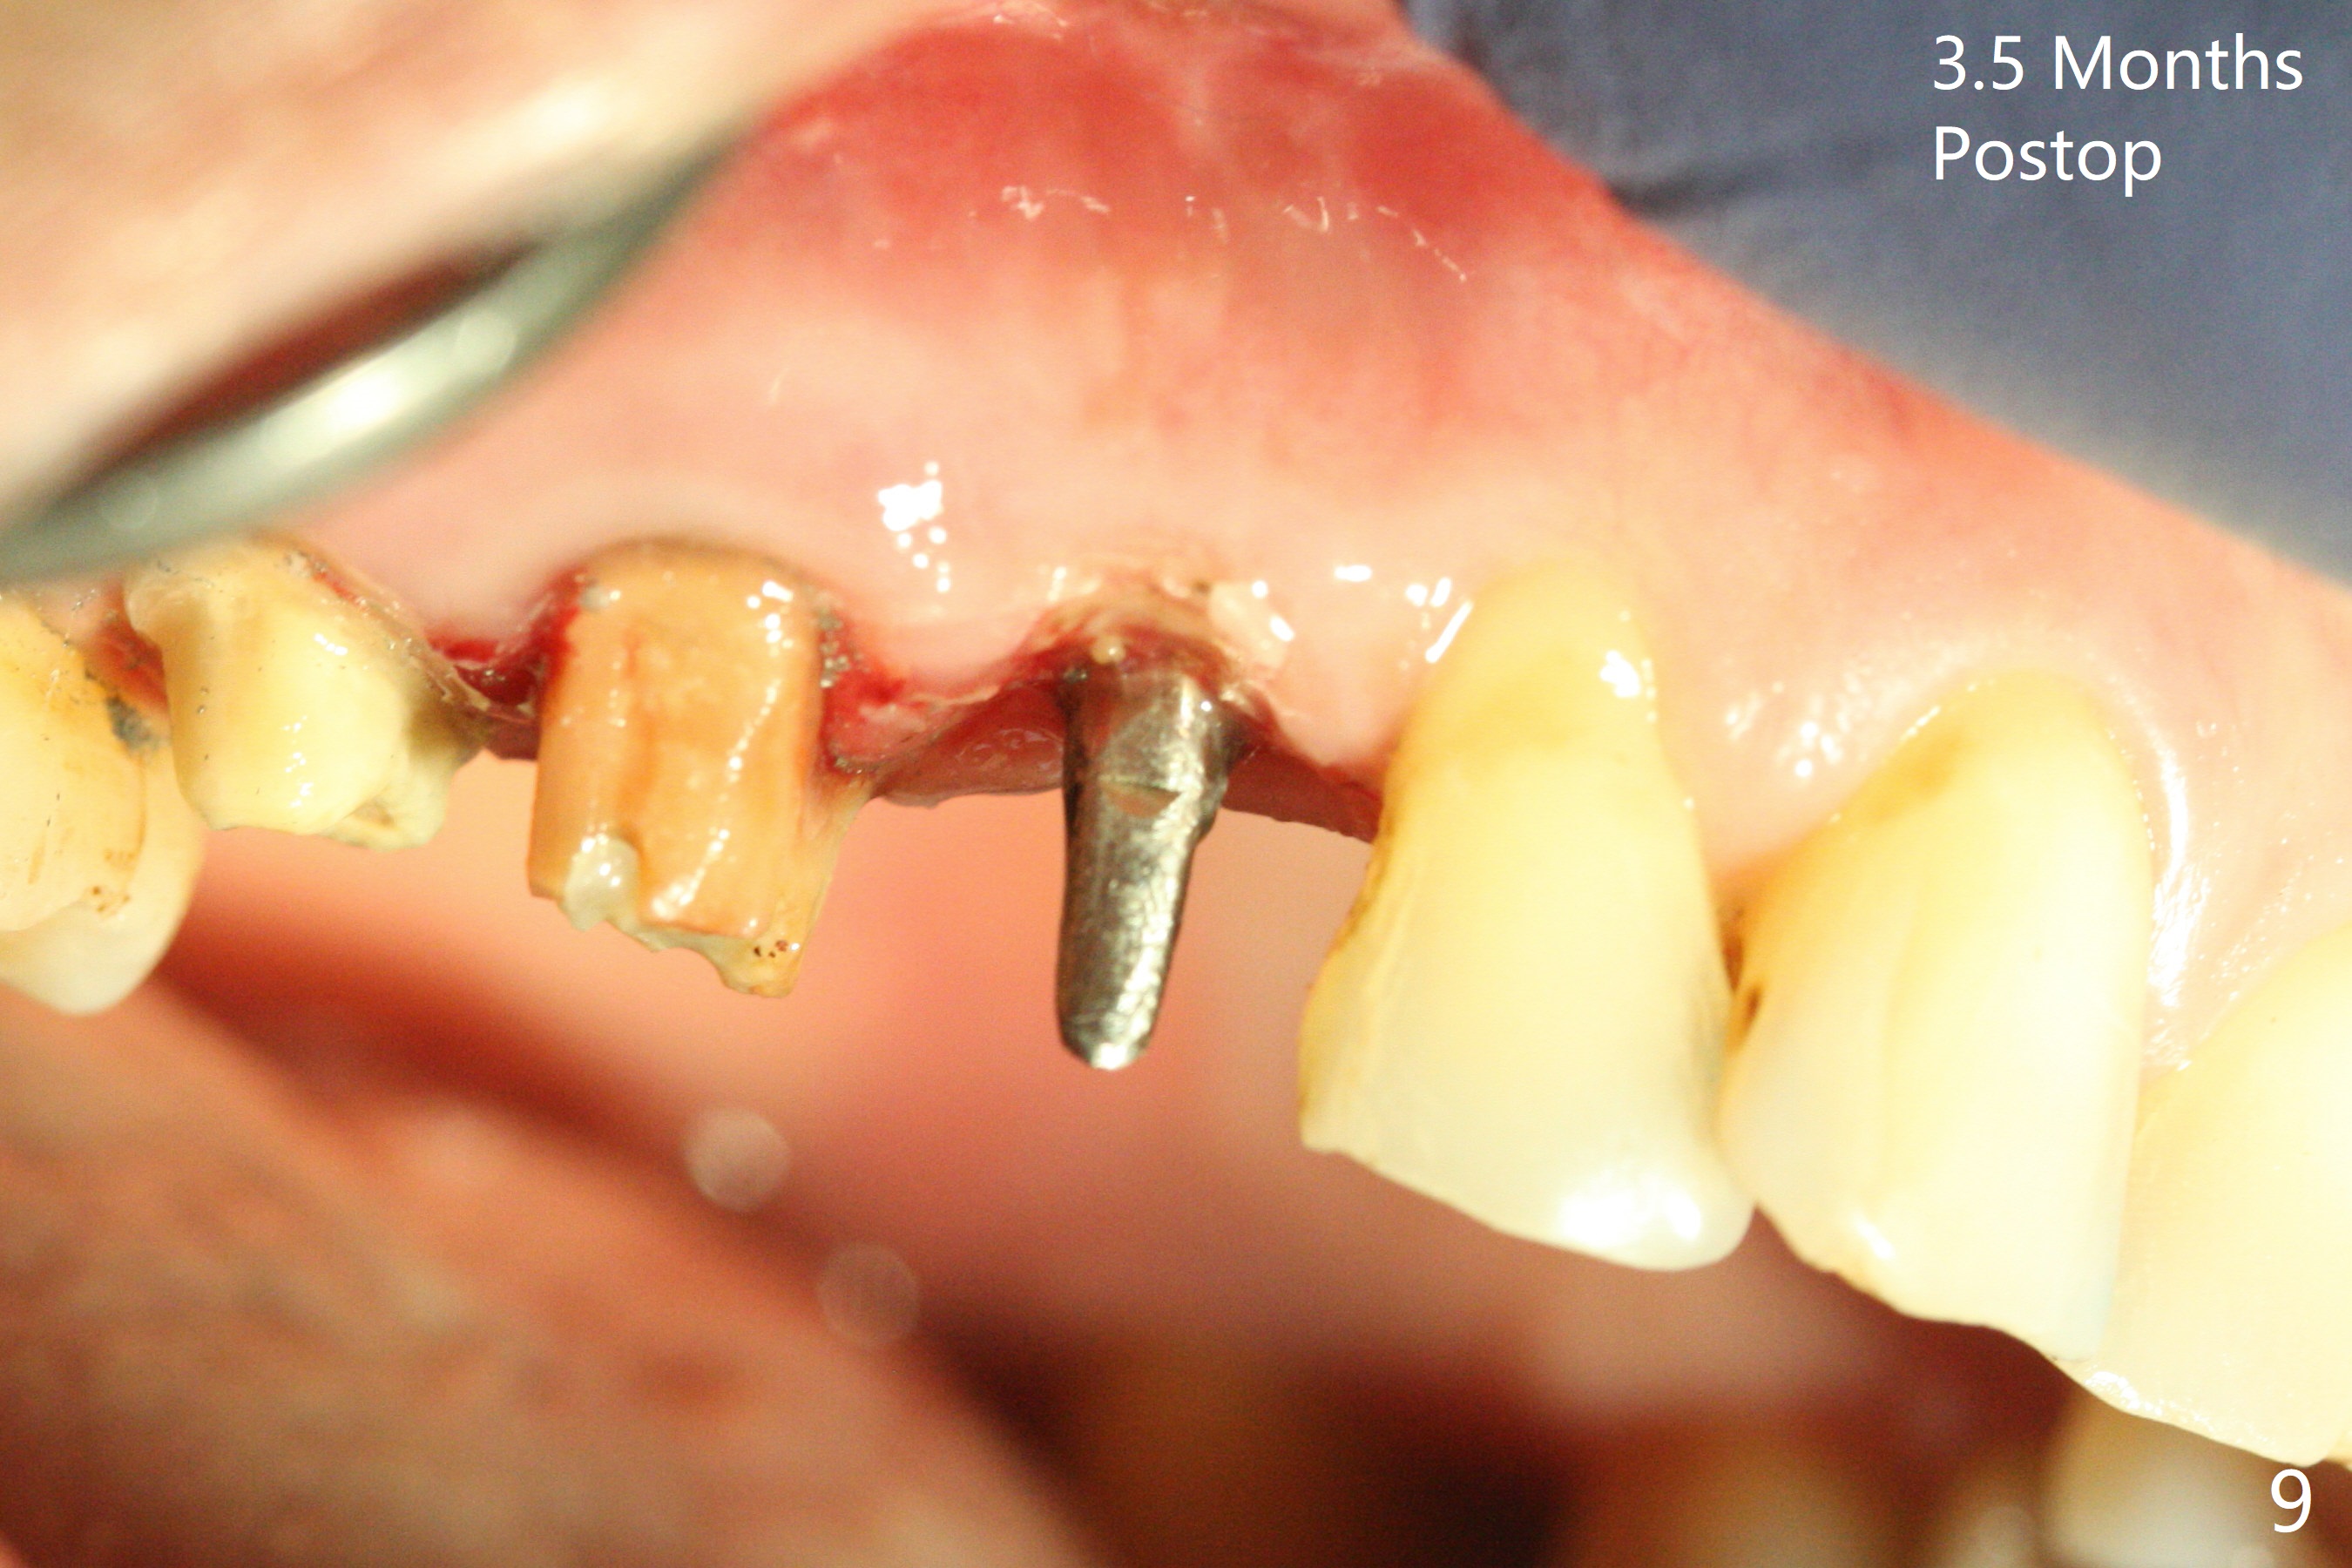

Osteotomy starts with guide and 2.2 mm drill for initial 3.5 mm palatal. A semilunar incision is made buccal to remove the impacted canine (#6 by sectioning). With direct vision buccal and palatal, the final osteotomy is finished free hand with 1.2 and 1.5 mm drills. Initially buccal perforation occurs, the osteotomy route is corrected later (Fig.1). When a 2.5x15 mm 1-piece implant is being placed, it perforates into the buccal concavity again. After redirection, the trajectory seems to be acceptable (Fig.2: CT coronal section). Three coronal implant threads are exposed partially palatal (Fig.3: CT 3-D palatal view). The implant is then turned 2-3 times with insertion torque reaching 40 Ncm. The incision is closed with suture following Osteogen plug placed in the most coronal portion of the socket (Fig.4 P) and allograft (*) in the remaining socket around the apical portion of the implant as well as palatal. The incision does not heal 1 month postop (Fig.5). PRF membrane will be placed next visit. Next visit the wound in fact is healing (Fig.6). PRF is unnecessary. The patient will return for impression 3 months postop. To be cosmetically pleasing, prepare local anesthetic and Laser for gingivectomy (Fig.7 red curved line). There is no bone loss around the implant 3.5 months postop (Fig.8). With topical, minor gingivectomy with laser creates papillae mesial and distal to the implant (Fig.9, 10 (incisal view)). After reline, there is appearance of a canine (Fig.11). The patient returns for impression 5 months postop; there is bone around the apex of the implant (Fig.12 *). The hard and soft tissues remain healthy when final restoration is delivered (Fig.13,14). The buccal plate reforms and #6 socket heals 12 months postop (6 months post cementation, Fig.15). The gingiva remains healthy at #4-6 nearly 2 years post cementation (Fig.16).